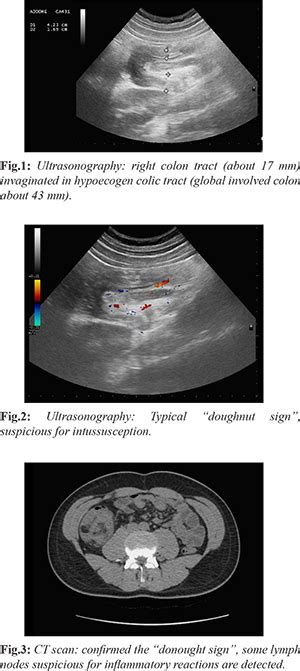

COLO-COLIC INTUSSUSCEPTION WITH LIPOMA – Case By Dr. Nitin Jadhav